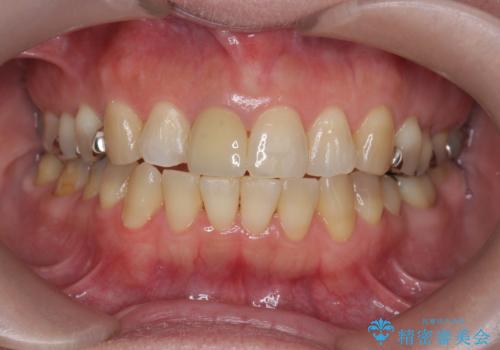

セラミッククラウン 歯ぐきの黒ずみの改善

- 十数年前に治療した前歯のクラウンの歯ぐきの位置が変化し、黒いラインが見え審美性の改善を求めて来院されました。

ファイバーコアのやりかえを行ったのち、金属を用いないジルコニアクラウンによる再補綴を行い前歯の審美性の向上を計画します。

近年前歯のクラウン製作に用いられるジルコニアクラウンは、金属を用いていないため経年的に歯ぐきの位置が変わっても黒いラインが見えることなく審美性の意地が期待できます。